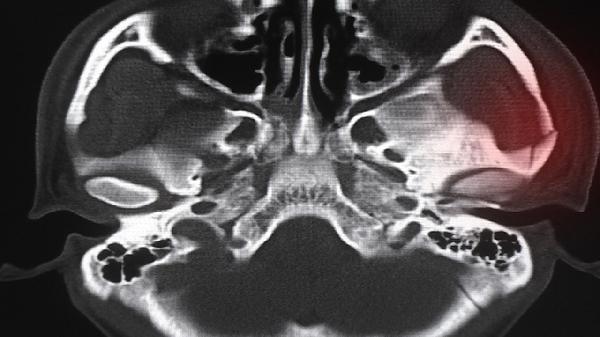

超短波治療通過高頻電磁波改善盆腔局部血液循環(huán),促進炎癥吸收。紅外線照射可緩解組織水腫,減輕下腹墜脹感。治療期間需保持皮膚清潔干燥,避免燙傷。物理治療通常需配合藥物使用,療程根據(jù)病情嚴重程度決定,急性期每日1次,慢性期隔日1次。